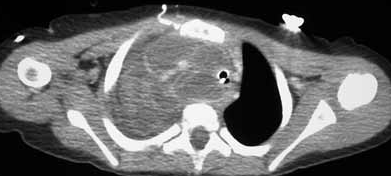

Antibiotic therapy was started. Because of increasing respiratory distress, the child underwent elective intubation and was admitted to the pediatric ICU. A CT scan of the neck and chest revealed a hypodense fluid collection with multiple septa extending from the retropharyngeal space into the mediastinum. There was significant compression of the trachea and thoracic vasculature. After the otolaryngologist and thoracic surgeon were consulted, the child underwent surgery. An infected cystic hygroma was found and excised.

DISCUSSION: In addition to the lateral neck mass, physicians in the emergency department noted dilated superficial vessels on the right anterior chest wall (Figure 1). A chest radiograph demonstrated a large density in the right upper lobe with a mediastinal shift to the left side (Figure 2).

The diagnosis of an infected cystic hygroma can be difficult because other processes—including retropharyngeal abscesses and infected branchial cleft cysts—also present with a neck mass, fever, and stridor. In many cases, advanced imaging is necessary to confirm the diagnosis. CT or MRI of a cystic hygroma typically reveals a multiloculated cystic mass. CT can delineate the size of the mass, although MRI more reliably identifies extension into the soft tissues, particularly neurovascular structures.In the presence of trauma or an upper respiratory tract infection, a cystic hygroma often becomes infected and grows rapidly, a process that produces fever and pain. Infiltration of the mass into the floor of the mouth, base of the tongue, epiglottis, or mediastinum can compromise the airway. This rapid enlargement of the mass secondary to infection accounts for the clinical signs and symptoms. In addition, our patient's clinical findings were consistent with superior vena cava syndrome (venous congestion, dysphonia, dyspnea, and dilated chest wall veins), which eventuated from thoracic compression of the hygroma (Figure 3).